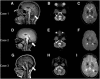

Mutations in POLR3A encoding the largest subunit of RNA polymerase III (Pol III) were found to be responsible for the majority of cases presenting with three clinically overlapping hypomyelinating leukodystrophy phenotypes. We uncovered in three cases without POLR3A mutation recessive mutations in POLR3B, which codes for the second largest subunit of Pol III. Mutations in genes coding for Pol III subunits are a major cause of childhood-onset hypomyelinating leukodystrophies with prominent cerebellar dysfunction, oligodontia, and hypogonadotropic hypogonadism.